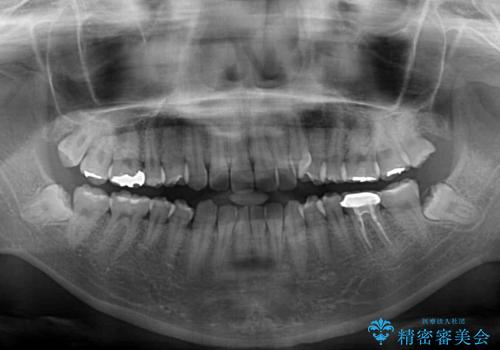

- 上顎の八重歯やデコボコを気にして来院された患者様です。

上顎歯列が狭窄していたため、急速拡大装置により上顎骨を側方に拡大しながら、ワイヤー装置にて矯正治療を行うこととしました。

上顎骨を拡大することで、八重歯やデコボコを歯列に収めることができ、下顎の歯が外に位置していた奥歯の咬み合わせも改善することができました。

スペースも短期間に獲得できるため、1年程度で治療を終えることができました。